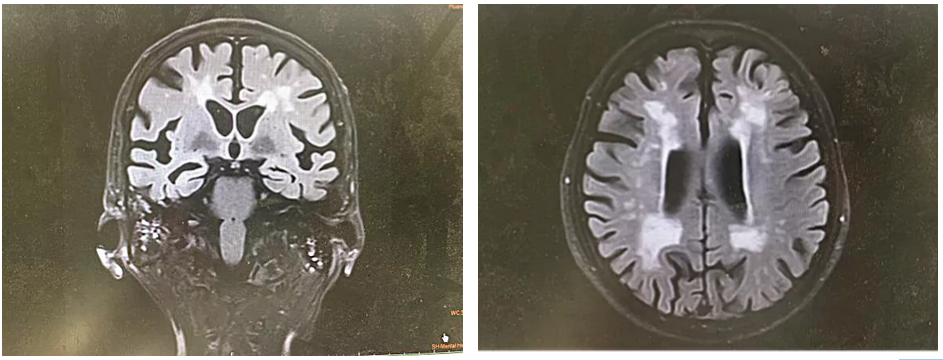

家里人带他去医院做了头颅MRI(磁共振成像),结果发现右侧颞叶、双侧放射冠区及额叶多发腔梗灶,还有重度脑白质疏松。

图/王大爷头颅MRI

王大爷有高血压、糖尿病等这些血管性问题,则是把我“娶”进门的条件。王大爷头颅MRI结果显示的多发腔梗灶、严重脑白质变性是我在王大爷脑子里“后院管理“的结果。